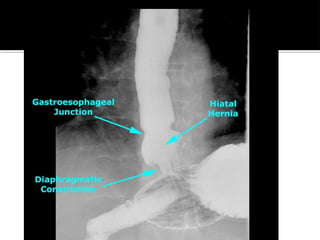

◾Herniation of the stomach through the

diaphragm into the chest cavity

Type I

 sliding hiatal hernia

◾ most common type (>95%)

◾ occurs at the GE junction

◾ stomach slides into the mediastinum

Type II

 paraesophageal hiatal hernia (<5%)

◾ herniation of stomach fundus through

diaphragm

◾ GE junction remains below diaphragm

◾ parallel to the esophagus

◾ Barium swallow

- may observe stomach in chest

cavity

◾ Usually an incidental finding